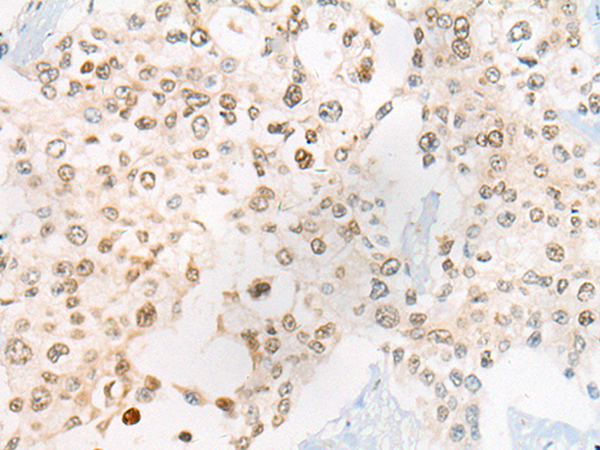

IHC positive control: |

Human thyroid cancer and Human prostate cancer |

IHC Recommend dilution: |

30-150 |